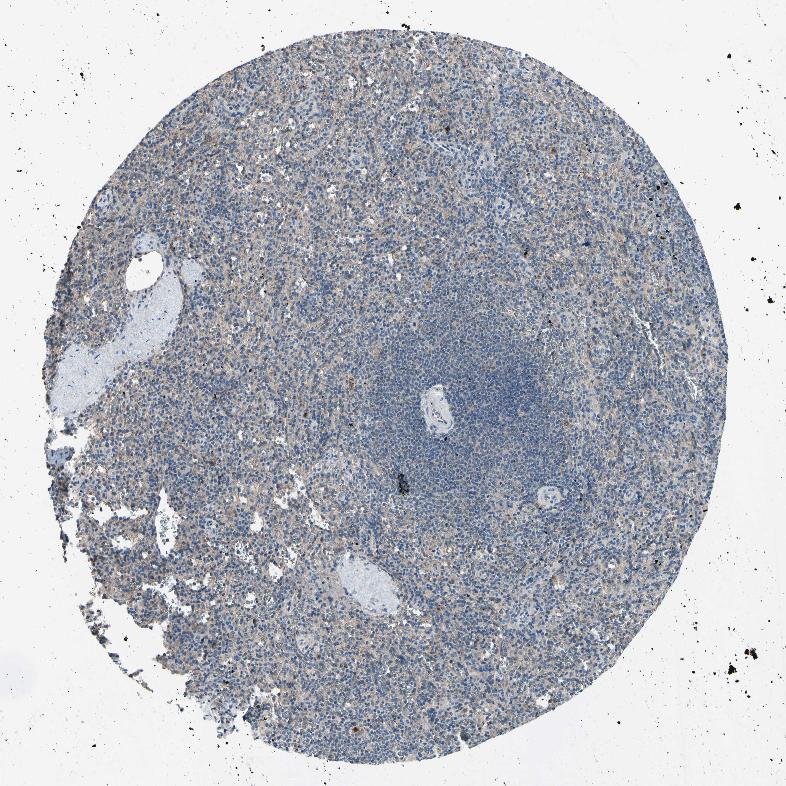

SPLEEN - Antibody stainingi

Antibody staining in the annotated cell types in the current human tissue is reported as not detected, low, medium, or high, based on conventional immunohistochemistry profiling in selected tissues. This score is based on the combination of the staining intensity and fraction of stained cells.

Each image is clickable and will lead to virtual microscopy that enables deeper exploration of all samples and also displays staining intensity scores, fraction scores and subcellular localization as well as patient and tissue information for each sample.

Antibody HPA010515

Cells in red pulp Not detected

Cells in white pulp Not detected